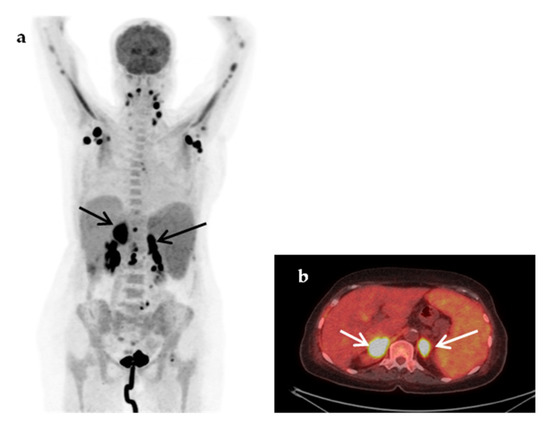

| Malignancy | 8 (16%) |

| Non-Hodgkin’s lymphoma | 5 |

| Hodgkin’s disease | 1 |

| Lung cancer | 1 |

| Relapse of urinary tract carcinoma | 1 |